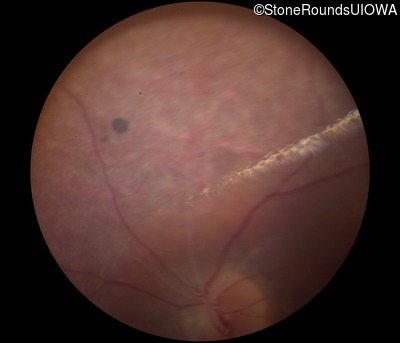

Fundus Photography - Right - 20/50 -3

Exemplar